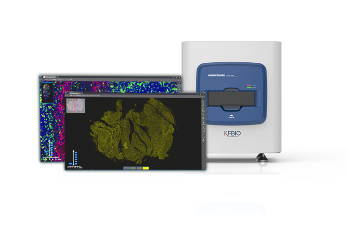

Digital Pathology Slide Scanner (PRO)

Digital Pathology Slide Scanner (PRO)

K-Viewer, a slide viewing software developed by KFBIO, allows pathologists to review and annotate digital slides for ease of diagnosis. It enables pathologists to swiftly access slides or cases on the desktop or remotely via the computer, smartphone, or tablet device.

KFBIO Digital Pathology Slide Scanner (PRO) is a world leader in the accuracy of movement, focus, and image processing, and its accurate whole slide imaging not only meets the requirements of digital slide viewing and operation but is also suitable for AI-assisted image analysis.